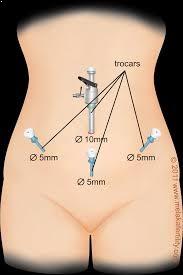

The uterus, ovaries, pelvic peritoneum, and Fallopian tubes may all be operated on during endoscopic reproductive surgery to promote fertility. Hysteroscopy and laparoscopy are included. Hysteroscopy is a telescopic examination of the uterine cavity from the inside to diagnose and correct cavity abnormalities that interfere with normal fertility. Laparoscopy is a minimally invasive surgical method that enables for surgery at the time of diagnosis by providing a panoramic and magnified image of the pelvic organs.

To determine the reason for infertility and ART (IUI Treatment or IVF Treatment) failures by examining the pelvic organs. After three failed COH and IUI procedures. To improve ART success rates, pelvic diseases such as uterine fibroid, endometriosis, pelvic adhesions, uterine septum, polyp, and others are treated to address infertility. Continual miscarriages as a pre-IVF screening test.

- Diagnostic

- Operative

- Salpingo-ovariolysis, fimbriolplasty, tuboplasty, salpingectomy, and other laparoscopic tubal operations

- Myomectomy using laparoscopy.

- Adhesiolysis, fulguration or excision of endometriotic implants, laparoscopic resection of chocolate cyst

- Post-infectious laparoscopic adhesiolysis

- Adnexal masses such as benign ovarian cysts, dermoid cysts, and paraovarian cysts are removed laparoscopically.